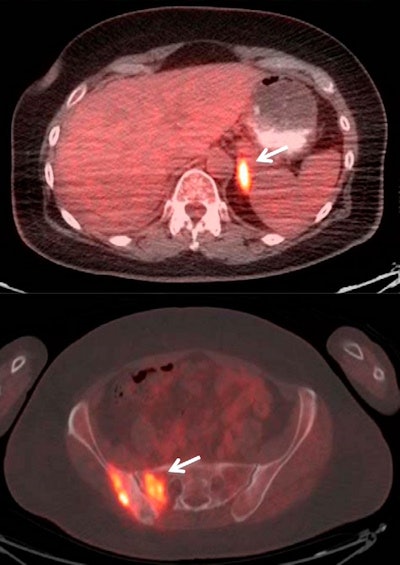

Fused PET/CT images of a 60-year-old woman with stage IIB adenocarcinoma of the right upper lobe of the lung. A routine fifth follow-up scan was requested without prior clinical suspicion of lung cancer recurrence one year after completion of primary treatment. PET/CT shows hypermetabolic, metastatic multiple osseous (arrow) and left adrenal lesions (arrow). The patient was started on a new chemotherapy regimen after the study. Images courtesy of JNM.Among the 285 scans, 157 (55%) were performed on patients who were not being treated prior to FDG-PET/CT. Of those 157 scans, 99 (63%) resulted in no treatment changes, and the patients continued with their normal follow-up. The other 58 scans (37%) resulted in a change in treatment.